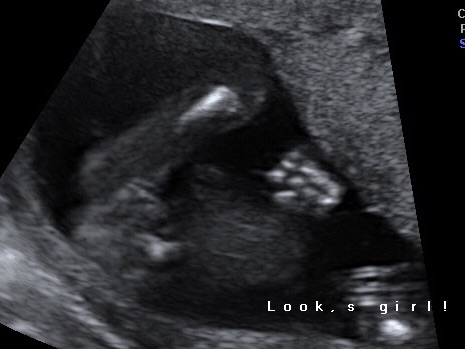

17 week potty shot

Hi all, I had a scan today dated 17weeks 4days and have been told it looks like a girl. I would be over the moon with this but am finding it hard to believe at the moment as we have a LOT of boys in the family! Would really appreciate your opinions. Thank you xx

It's tricky because sometimes the tech gets a better look than they are able to actually freeze and print for you. Idk if I would go solely based on THIS still but it does look girly to me even though baby is twisted a little.

Thank you for your reply. I have one other pic but don't think it's very clear! The tech didn't say she was unsure just said it's a girl! I'm hoping to get it confirmed at my 20 weeks scan but it's 3 weeks away and I'm sooo impatient!! xxAttachment 30987

Hmm neither of these pics are great. It's not not a girl, but I wouldn't be confident from these images alone. Looks like you'll need confirmation at the 20 week scan! If you're tech seemed sure then I'm sure it will be.